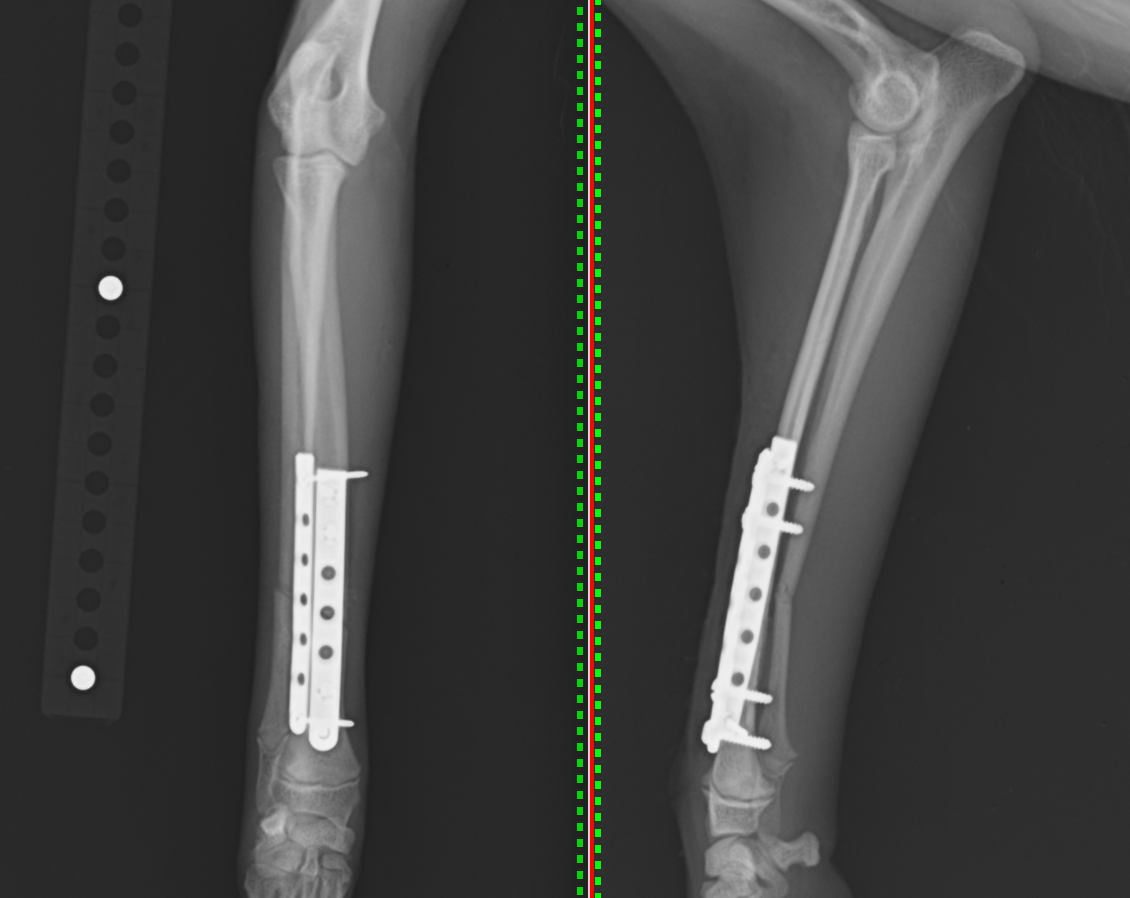

次にイタリアングレーハウンドの骨折を紹介いたします。イタグレは骨周囲の軟部組織が少なく、骨折治療を行ったにもかかわらず、骨が癒合せず細くなってしまう子がいます(癒合不全といいます)。そのため、最初の固定を強固に行うのはもちろんですが、骨癒合が進んだ段階で固定強度を落とす事が重要となります(ディスタビライゼーションといいます)。1枚のプレートでスクリューの数を減らす方法と2枚のプレートで1枚ずつ抜去していく方法がありますが、プレートが2枚の方がディスタビライゼーションを行った後の再骨折リスクを減らせるため(ロッキングという方法では抜去のタイミングが難しい)、当院ではそちらの方法で行っています。2枚のプレートを使った方法をオルソゴナルプレートといったり、ダブルプレート法と言ったりします。

2枚のプレートで固定しています。1つはLCPというプレートですが、スクリューは通常のスクリューを用いています。

術後のレントゲンです。足は真っ直ぐになり、骨折線もくっついているのが分かります。

正面のプレートを抜去した後のレントゲンです。骨折線がくっついているのがわかります。側面のプレートは残したままでも大丈夫です。

また別の子ですが、正面に1.5mm、側面に1.1mmのプレートを使用しています。

きちんとアライメント(足の向きとねじれ)を元の状態に戻して固定することが骨折治療において最も大切なことです。